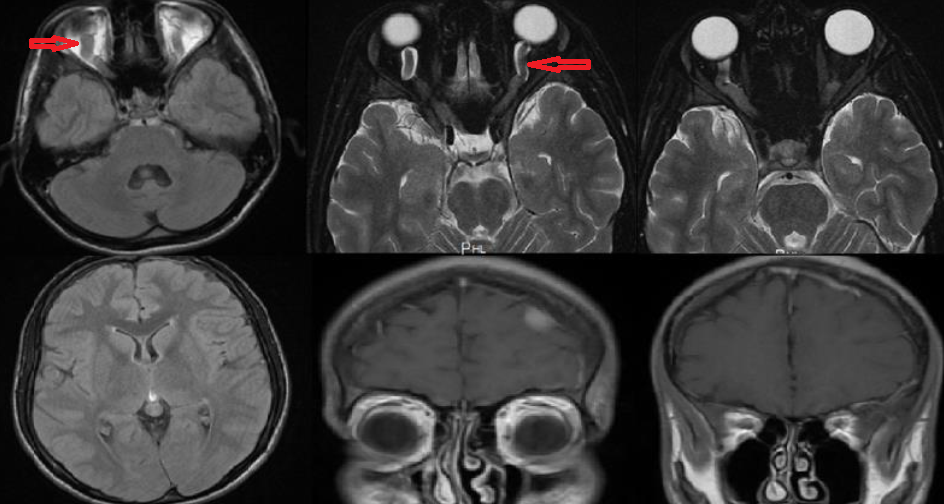

A 19-year-old male patient admitted to outpatient clinic due to the frequent episodes of headache that lasted up to 24 hours, accompanied by nausea and vomitting, localized to the bilateral temporal region. The hedache is pulsatile and showed partial response to analgesic drugs. Six months ago he was diagnosed with Rheumatoid artritis (RA) and hypotyridism because of the complaint of joint pain. The patient started to take methotrexate and prednisolone but he had stopped using these medicines voluntarily for the last 2 months. The family history was not remarkable. On the neurological exam, the lateral gaze was slightly restricted. Opthalmological exam was revealed bilateral papilledema, more pronounced on the right. Visual acuity was normal in the both eyes. The other system exams were normal. His hemoglobin concentration was 13.1 gr/dL,and his white blood cell (WBC) and platelet count were 11.28X103 and 223X103, respectively. Biochemical panel containing fasting blood glucose, bloon urea nitrogen (BUN), creatinine, aspartate transaminase (AST, alanin transaminase (ALT), sodium, potassium, calcium, vitamin B12, and folat was normal. Thyroid function tests (free T4: 0.53, Tiroid stimulating hormone (TSH): 4.28 ), thyroglobulin, antimicrosomal and antithyroglobulin antibodies were within normal limits. Erythrocyte sedimentation rate (44 hours) and C-reactive protein (11.6 mg/dL) were higher. Electrocardiogram revealed normal sinüs rhytm, and chest radiograph and full urine examination were normal. Antinucleer antibody (++); anti dsDNA, anti SS-A, anti SS-B, c-ANCA and p-ANCA were negative. Bilateral concentric constriction, more pronounced on the right , was observed on the computerized visual field exam (Figure 1). Brain Magnetic Resonance Imaging (MRI) showed swelling in the optic nerve sheats, rather than on the right, (Figure 2).

Figure 2 Brain MRI : Swelling in the optic nerve sheats.

In the analysis of cerebrospinal fluid (CSF) the opening pressure was 370 mmH2O, CSF protein and electrolyte levels were witin normal limits, and there was not pleocytosis, serology and culture were negative. The patient had started to take acetozolamide 750 mg/d and dexametazone 12 mg/d. In the 7th day of treatment the opening pressure of CSF was measured as 290 mmH2O. Cytologic exam of CSF showed atypical lymphoid cells (Figure 3). In bone marrow biopsy, atypical lymphoid cells were diffuzely stained with Pax 5 by immunohistochemical method (Figure 4). The patient was diagnosed as precursor lymphoblastic leukemia/lymphoma. The patient who transferred to the Hematology clinic died on the 26th day of admission because of the sepsis on 20th day of admission.